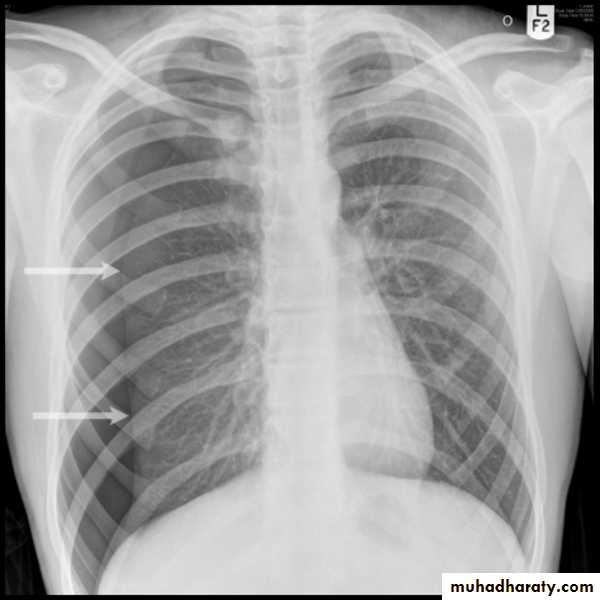

X-ray pneumothorax

Vascular and chest surgery practical

X-ray tension pneumothorax